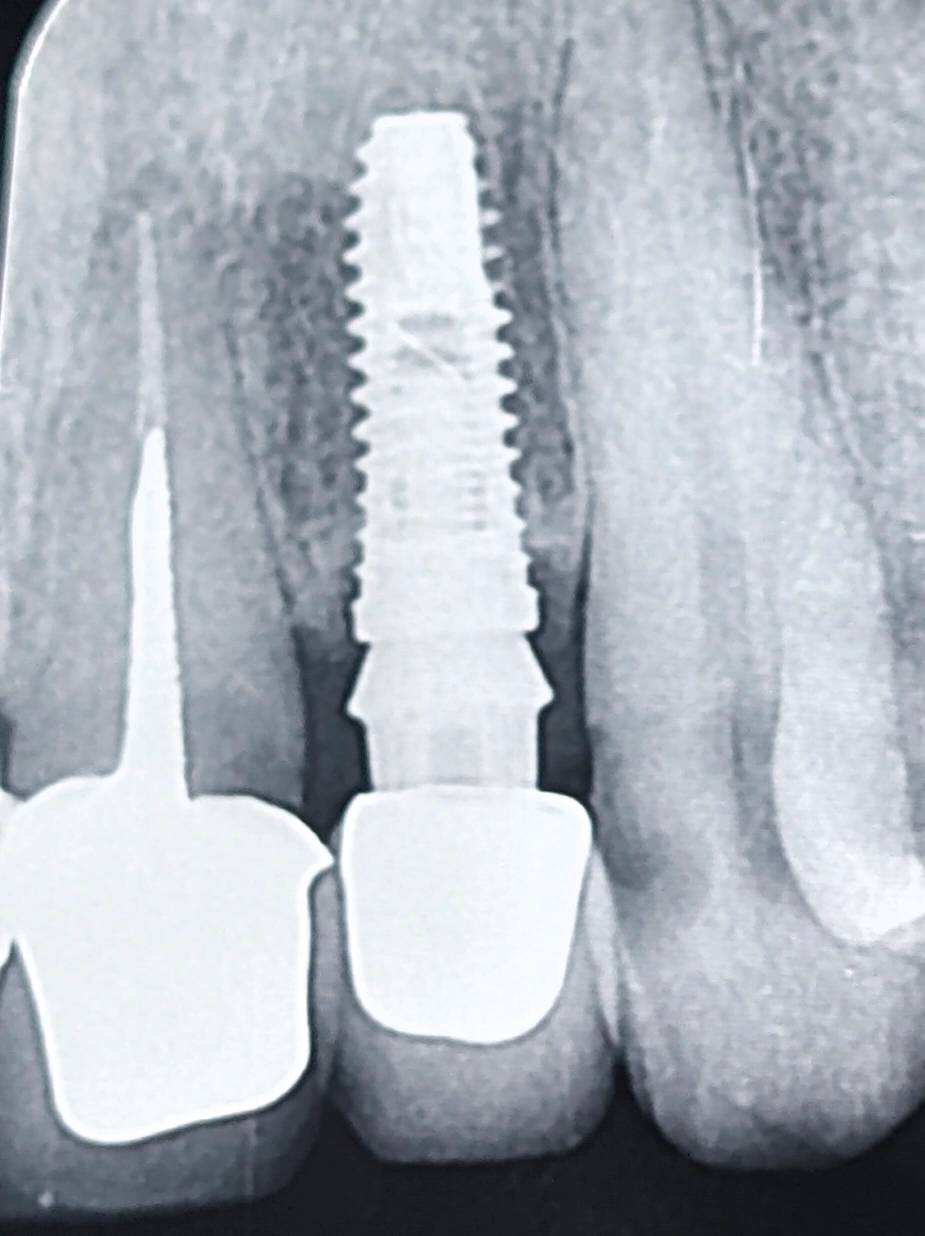

بیمار با یک روکش ایمپلنتی در ناحیه قدامی مراجعه کرده بود.

در بررسی رادیوگرافی، اختلاف قابل توجهی بین فینیشلاین اباتمنت و مارجین روکش دیده میشد.

بهعبارتی، مارجین روکش پایینتر از فینیشلاین قرار گرفته بود و یک فاصله عمودی ایجاد شده بود.

اما در این کیس، شواهد نشان میداد که روکش از ابتدا به همین فرم ساخته شده است.

نه از نظر فریم و نه از نظر پرسلن، نشانهای از گیر یا تراش اضافی وجود نداشت.

بنابراین، منشأ خطا به احتمال زیاد در مرحله قالبگیری بوده است.

در این سناریو این احتمال وجود دارد که دندانپزشک در جلسه قالبگیری، اباتمنت را بسته و قالب نهایی را تهیه کرده باشد،

اما فینیشلاین بهدرستی در قالب ثبت نشده است.

در نتیجه، لابراتوار بر اساس اطلاعات ناقص، روکش را کوتاهتر از فینیشلاین ساخته است.

پیامد این خطا، ایجاد فاصله بین مارجین روکش و فینیشلاین است؛

و این فاصله میتواند منجر به تجمع پلاک، التهاب بافت نرم و کاهش پیشبینیپذیری درمان شود.